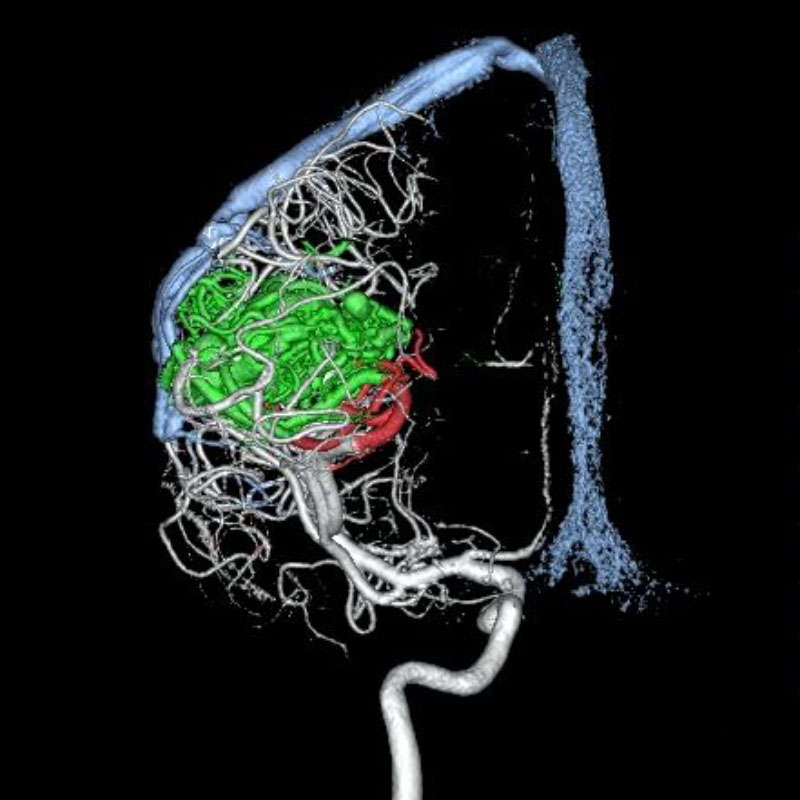

脳動静脈奇形

血管塞栓術

松田/濵田/元永